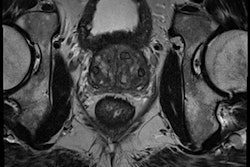

The group, led by Dr. Jordi Broncano Cabrero from Córdoba, showed precisely how DWI can depict the presence of myocardial edema in ischemic and inflammatory heart disease, and also can help in the characterization of cardiac masses as well as for follow-up and treatment monitoring in both acute myocarditis and cardiac masses. To get the full story, click here.